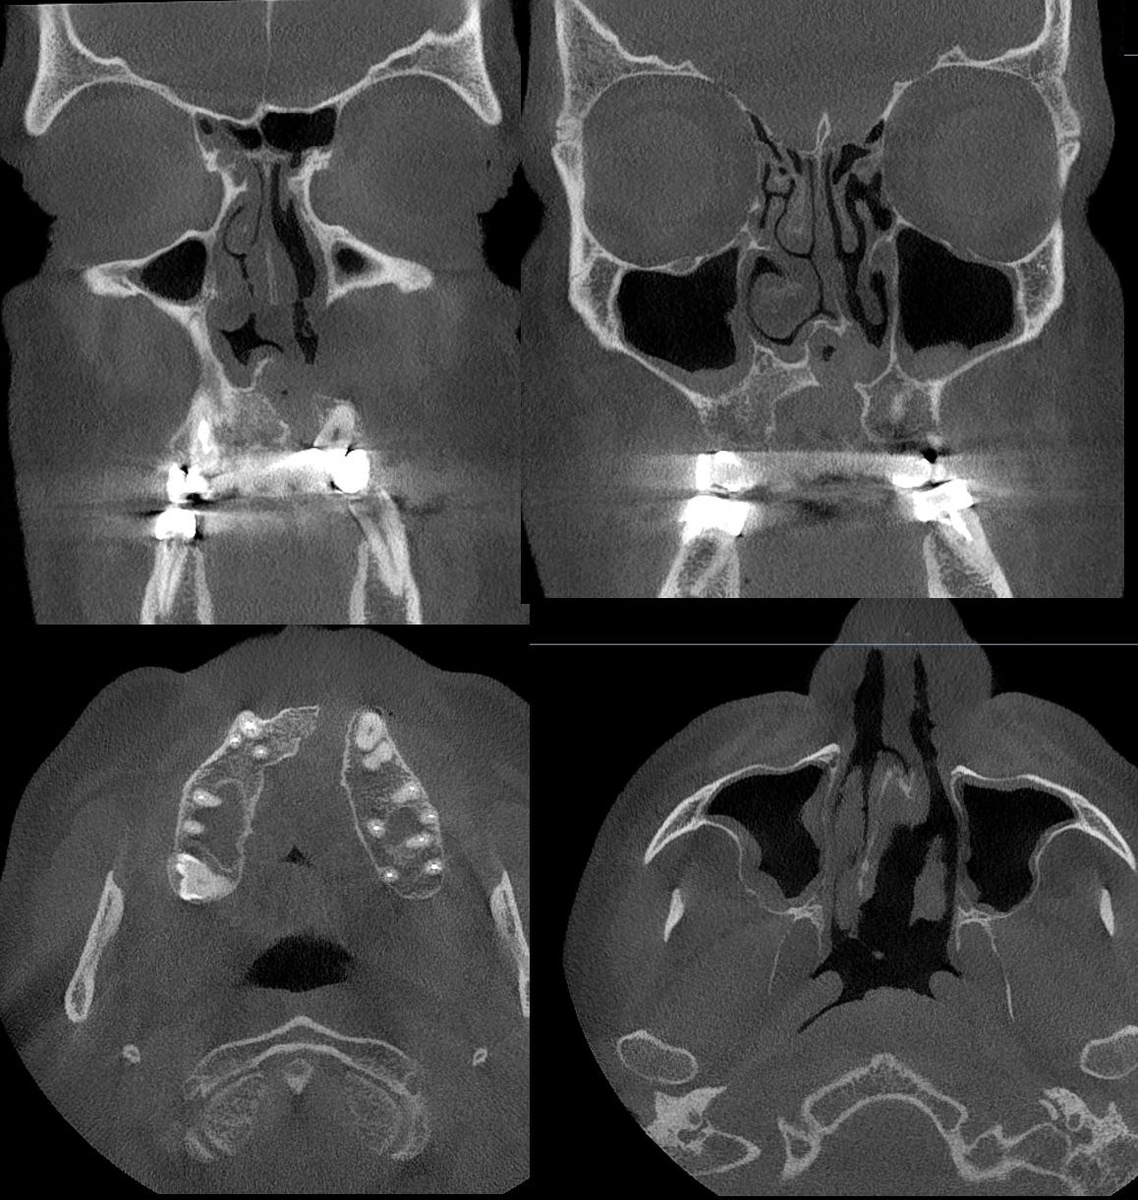

". Какие мысли? Представлена отоскопия и КЛКТ ОНП. Есть довольно специфические изменения, поэтому без подсказок)

Какие мысли? Представлена отоскопия и КЛКТ ОНП. Есть довольно специфические изменения, поэтому без подсказок)